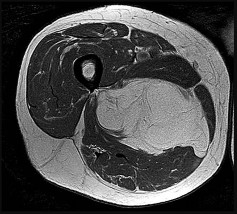

This patient has a dedifferentiated liposarcoma within a preexisting atypical lipomatous tumor. The imaging demonstrates a large fatty mass with increased internal septations proximally (the atypical lipomatous tumor) and a solid enhancing mass distally (the dedifferentiated portion). A biopsy reveals a high-grade liposarcoma. The other diagnostic responses do not reflect sarcomatous transformation of the lesion.